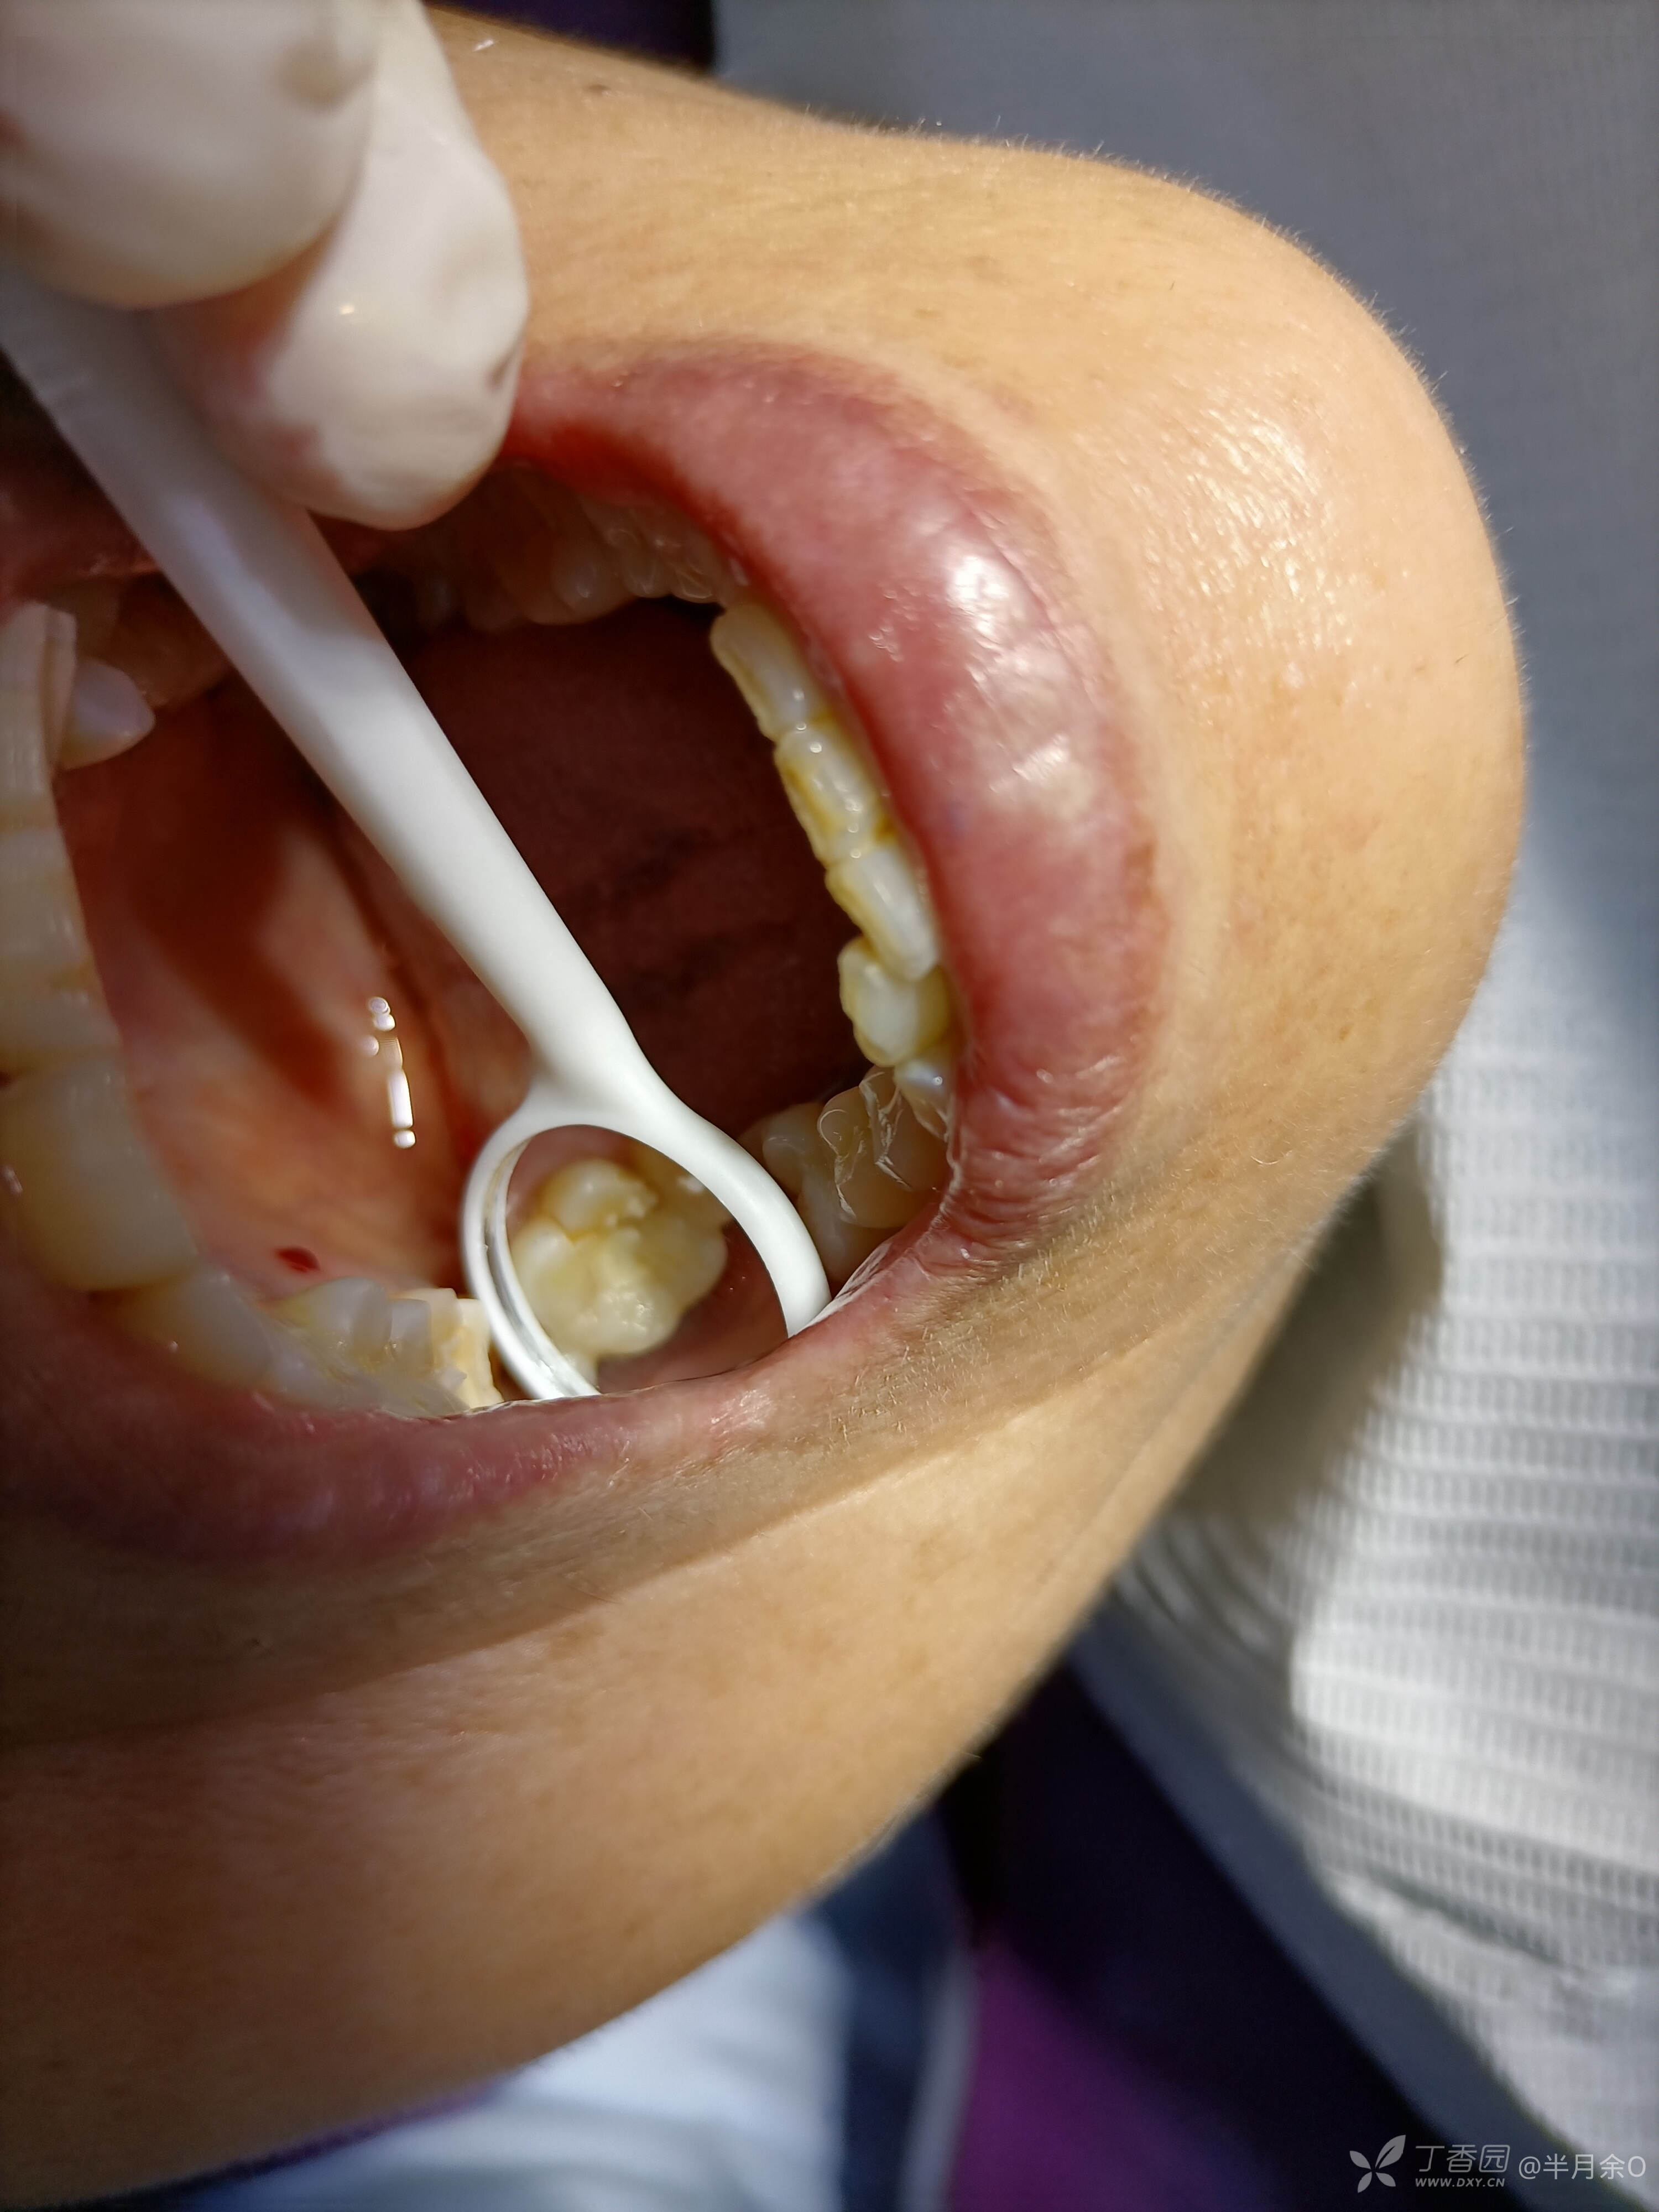

患者年龄60,2021.5.29因牙痛,夜间痛就诊,右上6检查隐裂,建议根管治疗后冠修复,患者要求拔除,考虑后下午来治疗6.6根备,6.17根充,患者拒绝冠修复,7.13腭尖折断至龈下约2mm,拔除腭尖,分享。